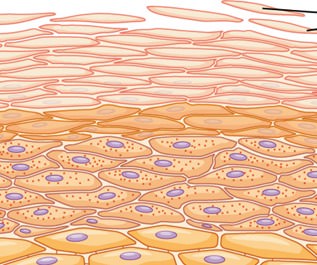

SISTEM INTEGUMENTARI

KULIT adalah organ yang terbesar pada tubuh manusia yang berperanan antara lain menjadi batas pelindung organ-organ dalaman dari terdedah pada mikro organisma dari persekitaran luar.

Kulit juga merupakan satu agen ‘sensori’ dimana apa jua yang berlaku keatasnya akan dapat dirasakan melaui jaringan sensori dan saraf yang memberi isyarat kepada otak untuk tindakan selanjutnya.

Apakah bicara ALQuran tentang kulit? Firman Allah pada ayat 56 surah An-Nisa’ memberitahu bahawa reseptor deria rasa sakit pastinya terdapat pada kulit yang menjurus kepada cabang anatomi yang disebut sistem Integumentari.

Sesungguhnya orang-orang yang kufur ingkar kepada ayat-ayat keterangan Kami, Kami akan membakar mereka dalam api Neraka. Tiap kali KULIT mereka hangus, Kami gantikan untuk mereka KULIT yang lain supaya mereka merasa azab sengsara dan (ingatlah) sesungguhnya Allah adalah Maha Kuasa, lagi Maha Bijaksana. (An-Nisa’ 56)

Pada ayat 23 surah Az-Zumar dikhabarkan bahawa adanya semacam deria rasa pada kulit ketika wujudnya rasa ketakutan atau keresahan sepertimana kita kadangkala menyebut “berdiri bulu roma”. Kadangkala kita merasakan seperti ada rasa tusukan pada kulit dan juga rasa seperti ada semut bergerak dipermukaan kulit. Demikianlah beberapa sifat kulit yang bertukar mengikut kewujudan sensori yang menyentuh perasaan atau saraf. Sentuhan pada kulit juga dapat merangsang saraf selari dengan cara sentuhan dilakukan.

Allah telah menurunkan sebaik-baik perkataan iaitu Kitab Suci Al-Quran yang bersamaan isi kandungannya antara satu dengan yang lain (tentang benarnya dan indahnya), yang berulang-ulang (keterangannya, dengan berbagai cara); yang (oleh kerana mendengarnya atau membacanya) kulit badan orang-orang yang takut kepada Tuhan mereka menjadi seram; kemudian kulit badan mereka menjadi lembut serta tenang tenteram hati mereka menerima ajaran dan rahmat Allah. Kitab Suci itulah hidayat petunjuk Allah; Allah memberi hidayat petunjuk dengan Al-Quran itu kepada sesiapa yang dikehendakiNya (menurut undang-undang peraturanNya) dan (ingatlah) sesiapa yang disesatkan Allah (disebabkan pilihannya yang salah), maka tidak ada sesiapa pun yang dapat memberi hidayat petunjuk kepadanya.

Kulit juga dikhabarkan mempunyai kuasa menyimpan memori data yang akan dikeluarkan kembali pada Hari Kiamat nanti seperti mana difirmankan pada ayat 19-21 surah Fussilat.

Tiga potong ayat ini memberi bayangan bahawa kulit yang menjadi pelindung tubuh kita akan menjadi saksi diHari Kiamat nanti. Sekiranya kita mendalami ilmu DNA dan kaitannya pada kulit kita akan sedikit sebanyak mendapat pencerahan.

Pada pertengahan tahun 2007 majalah “Neuroscience” telah menerbitkan satu kajian saitifik terhadap kulit dimana mereka mendapati wujudnya sel yang mengandungi molekul CaMKII yang bertanggungjawab dalam menyimpan ‘memori’.

Walaupun kajian tersebut masih belum diterima secara mutlak oleh masyarakat saintis namun AlQuran sudah memberi bayangan kebenarannya.